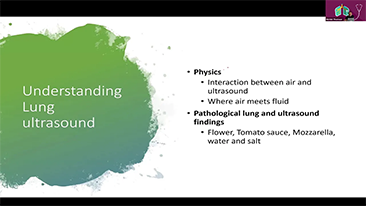

?? ??? ???? ??? ? ?????

??? ?? ??? ?? ???? ? ??? ?? ??? ?? ??? ??? ??? ???. ???? ??? UWN+ ?? ?? ??? ?? MI??? ??? ??? ?? ?? ??? ?? ?? ?? ???, ?? ?? ?? ???? ??? ? ????.